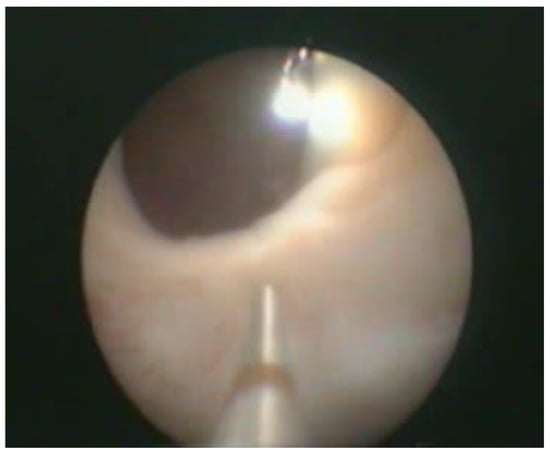

Transurethral cystoscopy displayed a wide open bladder neck at the beginning of the procedure (Figure 5). Under guidance by antegrade suprapubic endoscopy, transurethral retrograde bladder neck injection was performed at the 3 o’clock and 9 o’clock positions (Figure 6). Subsequently, bladder neck injection at the 6 o’clock and 12 o’clock positions was performed through antegrade percutaneous suprapubic endoscopy. Direct antegrade and retrograde visualization confirmed effectiveness of the luminal occlusion (Figure 7). As a (positive) consequence of effective injection, visibility of the optimal location for injection was compromised with increasing volume of the bulking agent. The combined injection technique is helpful to reduce this limitation as much as possible.

Figure 7.

Retrograde cystoscopy confirming effectiveness of luminal occlusion (before injection: see Figure 5).